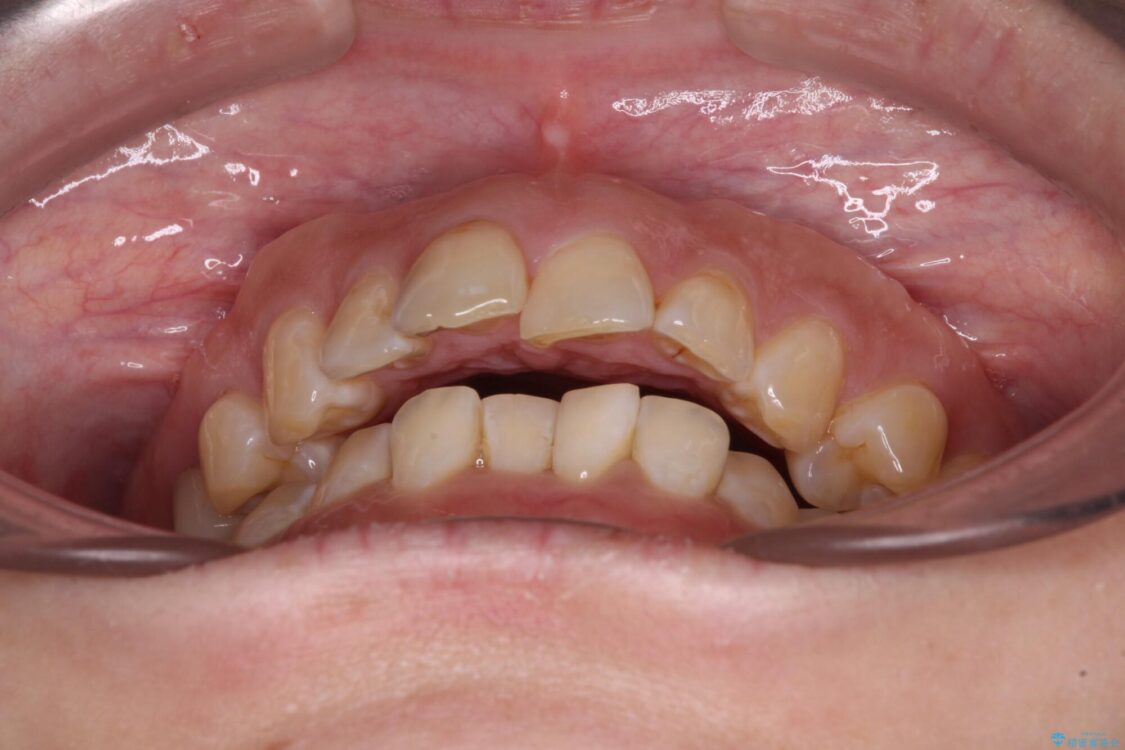

飛び出た上の前歯を気にして来院された患者様です。

奥歯の咬み合わせは、上顎歯列が理想的な一よりも数mm前方にある状態でした。

治療前

• 【モニター】飛び出た前歯を整えたい ワイヤー矯正治療 治療前画像